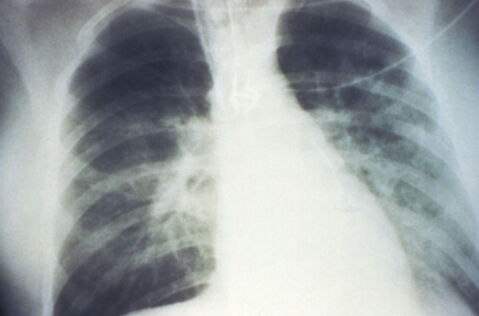

Chang machte bei der OP kleine Schnitte zwischen Mehrkars Rippen, bevor sie das “Da-Vinci-Xi-Robotersystem” einsetzte.

Der Roboter half dabei, die kranken Lungenflügel zu entfernen.

Dann wurde mit Hilfe der “präzisen Roboter-Technik” im Körper der schwerkranken Patientin die Lunge eingenäht.

Laut der Bild sei die Roboter-OP bei der Patientin Cheryl Mehrkar ein “wichtiger Meilenstein, weil die Mehrheit der Betroffenen auf eine Doppel-Lungentransplantation angewiesen ist und nicht auf die eines Lungenflügels alleine”.